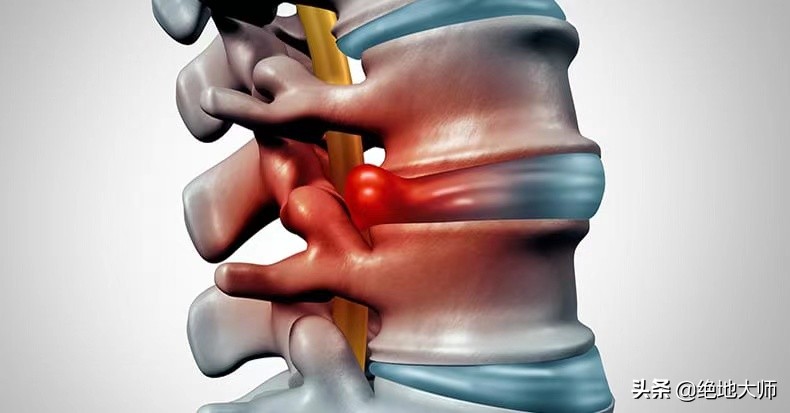

4. 腰椎神经根病(坐骨神经痛)的评估和神经调控康复治疗

课程大纲:

坐骨神经痛的原因和生理机制;

神经根性腰痛的功能评估;

坐骨神经痛的临床治疗目标;

不同类型坐骨神经痛的神经调控康复治疗。